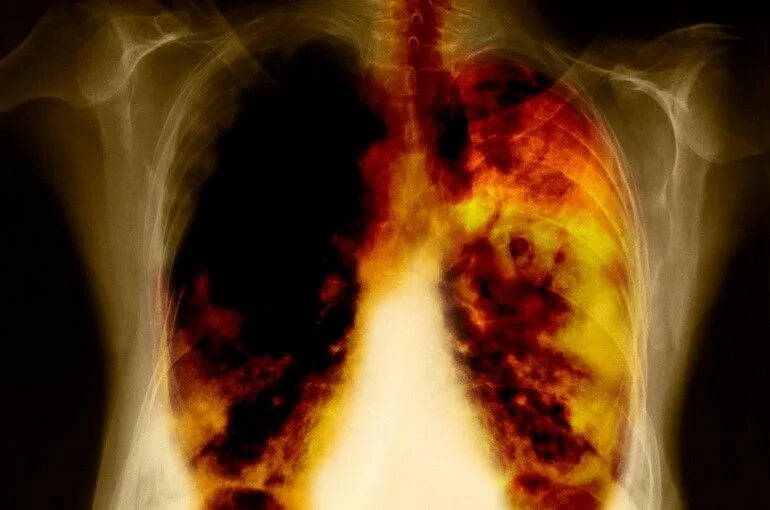

Снимок курильщика